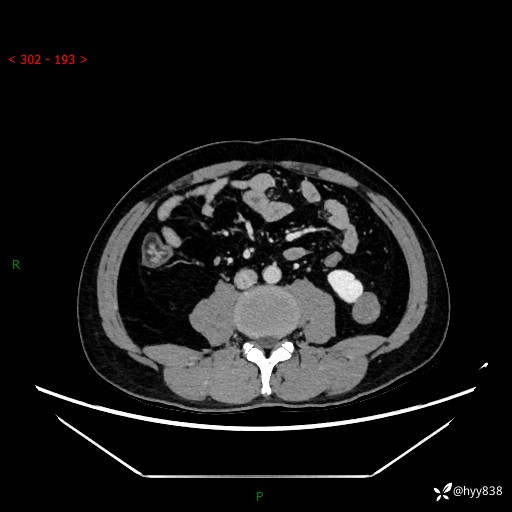

中年男性,左侧腰背部间断性胀痛不适。第一眼“乳头或囊肿”,有无意外---(有结果)

【患者信息】:41岁/男

【主诉】:左侧腰背部间断性胀痛不适1周

【现病史及既往史】:患者1周前无明显诱因出现左侧腰部疼痛,呈间断性胀痛,休息后可缓解,无放射痛,偶可见肉眼血尿,无血块,无尿频尿急尿痛,无夜尿增多,无畏寒发热、咳嗽咳痰等症状。于我院查双肾CT示:左肾占位性病变,左肾下极囊性病变,左肾轻度积水,胆囊多发结石。今为求进一步诊治来我院,门诊以“左肾占位性病变”收治入院。 起病以来,患者精神佳,饮食、睡眠良好,大便正常,小便如上诉,体力体重无明显变化。

【检查】:肾脏CT平扫+增强